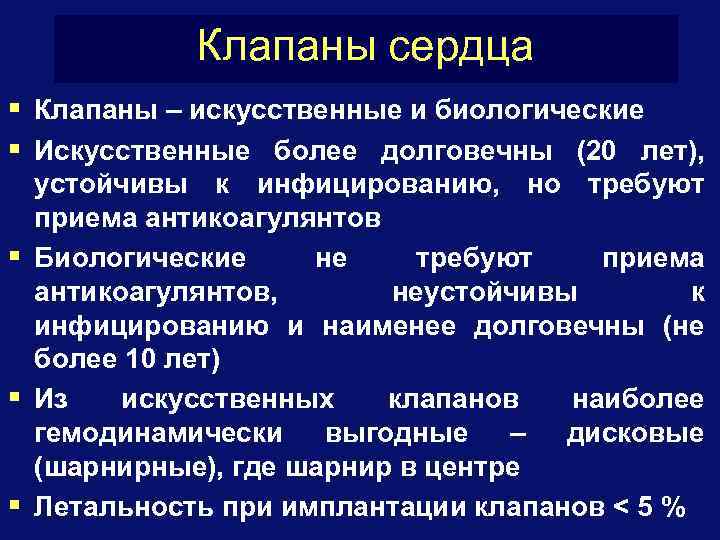

Клапаны сердца § Клапаны – искусственные и биологические § Искусственные более долговечны (20 лет), устойчивы к инфицированию, но требуют приема антикоагулянтов § Биологические не требуют приема антикоагулянтов, неустойчивы к инфицированию и наименее долговечны (не более 10 лет) § Из искусственных клапанов наиболее гемодинамически выгодные – дисковые (шарнирные), где шарнир в центре § Летальность при имплантации клапанов < 5 %